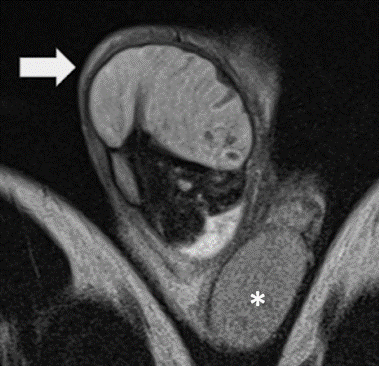

La RM evidenció TD aumentado de tamaño, horizontalizado y ascendido, con señal hiperintensa en secuencias T1 y T2, sin captación de contraste (Figura 1a, 1b).

TD ascendido, horizontalizado, con moderado aumento de tamaño y señal heterogénea predominantemente hipointensa (flecha) comparar con testículo contralateral de características conservadas (*). Origen: Servicio de Diagnóstico por Imágenes. Hospital Italiano de Buenos Aires. Buenos Aires, Argentina. 2021.

Figura 1a Imagen coronal secuencia T2

TD con pérdida de su morfología ovoidea presenta ausencia completa de captación de contraste en todo el parénquima (Flecha) compararse con TI que muestra captación normal (*). Origen: Servicio de Diagnóstico por Imágenes. Hospital Italiano de Buenos Aires. Buenos Aires, Argentina. 2021.

Figura 1b Imagen coronal secuencia T1